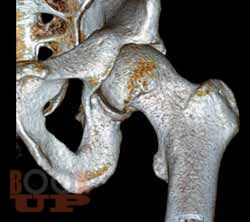

В основу книги положен многолетний опыт ультразвуковых исследований тазобедренного сустава в многопрофильной клинике с развитыми ревматологической и ортопедической службами. Проанализирован опыт отечественных и зарубежных авторов, суммированы результаты многочисленных оригинальных собственных исследований. Подробно освещены вопросы топографической и ультразвуковой анатомии тазобедренного сустава, технические особенности проведения исследования в том числе с использованием контрастных препаратов, проведения внутрисуставных инъекций под контролем ультразвукового исследования. Подробно описаны особенности ультразвуковой визуализации неизмененного тазобедренного сустава, широкого спектра патологических состояний и заболеваний дегенеративно-дистрофического, травматического, воспалительного генеза при использовании новейших и инновационных технологий эхографии. Дано подробное описание ультразвуковой картины при различных состояниях сустава: от асептического некроза головки бедренной кости, артрита, трохантерита, бурситов до бедренно-ацетабулярного импинджмента, ARS- и хамстринг-синдромов. В монографии представлены рациональные варианты и алгоритм диагностического поиска при патологии тазобедренного сустава с применением методов лучевой визуализации, определено оптимальное место ультразвукового исследования, даны подробные варианты описательной и заключительной частей ультразвуковых протоколов.